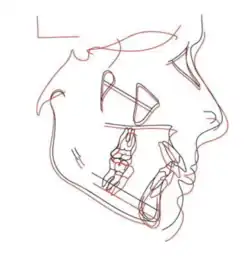

Figure 9: Cephalometric changes: pre-treatment (black lines), pre-debond (red lines)[22]

With the help of CBCT which produces detailed 3D images, the skeletal effects of the condyle (the curved part of the mandible which fits into the TMJ) was recorded.[23]

The size of the condyle, distance between the two condyles, and the length of the mandible increased. The twin block appliance enabled the growth of the condyle in a backwards and upwards direction. Based on cephalometric analysis, as given in Figure 21, the angle of SNB (the position of the mandible to the base of the skull) increased, and the angle of SNA (the position of the maxilla to the base of the skull) and ANB (anteroposterior relationship between the maxilla and mandible) decreased thus reducing the Class II skeletal malocclusion.[24]